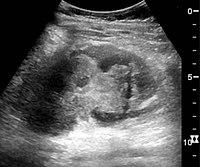

In medical imaging, the acute changes in the kidney are often examined with renal ultrasonography as the first-line modality, where CT scan and magnetic resonance imaging (MRI) are used for the follow-up examinations and when US fails to demonstrate abnormalities. In evaluation of the acute changes in the kidney, the echogenicity of the renal structures, the delineation of the kidney, the renal vascularity, kidney size and focal abnormalities are observed.[16] CT is preferred in renal traumas, but US is used for follow-up, especially in the patients suspected for the formation of urinomas. A CT scan of the abdomen will also demonstrate bladder distension or hydronephrosis. However, in AKI, the use of IV contrast is contraindicated as the contrast agent used is nephrotoxic.

16. ^ a b c d Content initially copied from: Hansen, Kristoffer; Nielsen, Michael; Ewertsen, Caroline (2015). "Ultrasonography of the Kidney: A Pictorial Review". Diagnostics. 6 (1): 2. doi:10.3390/diagnostics6010002. ISSN 2075-4418. PMC 4808817. PMID 26838799. (CC-BY 4.0) Archived 2017-10-16 at the Wayback Machine